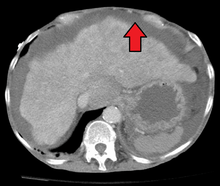

Ultrasound is routinely used in the evaluation of cirrhosis. It may show a small and nodular liver in advanced cirrhosis along with increased echogenicity with irregular appearing areas. Other findings suggestive of cirrhosis in imaging are an enlarged caudate lobe, widening of the liver fissures and enlargement of the spleen. An enlarged spleen (splenomegaly), which normally measures less than 11–12 cm in adults, is suggestive of cirrhosis with portal hypertension in the right clinical setting. Ultrasound may also screen for hepatocellular carcinoma, portal hypertension, and Budd-Chiari syndrome (by assessing flow in the hepatic vein).

Other tests performed in particular circumstances include abdominal CT and liver/bile duct MRI (MRCP).